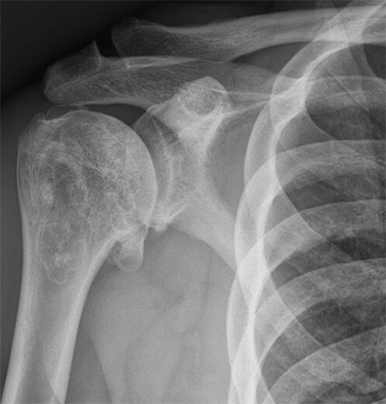

Pyrocarbon shoulder hemiarthroplasty

- Case Examples from Dr. Lee’s practice:

- This is a case example of a patient in his 40s who presented to us with severe shoulder pain, inability to work out and even raise his shoulder to chest level! At 6 months postoperatively he is back to the activities that he wants, keeping him active and healthy again